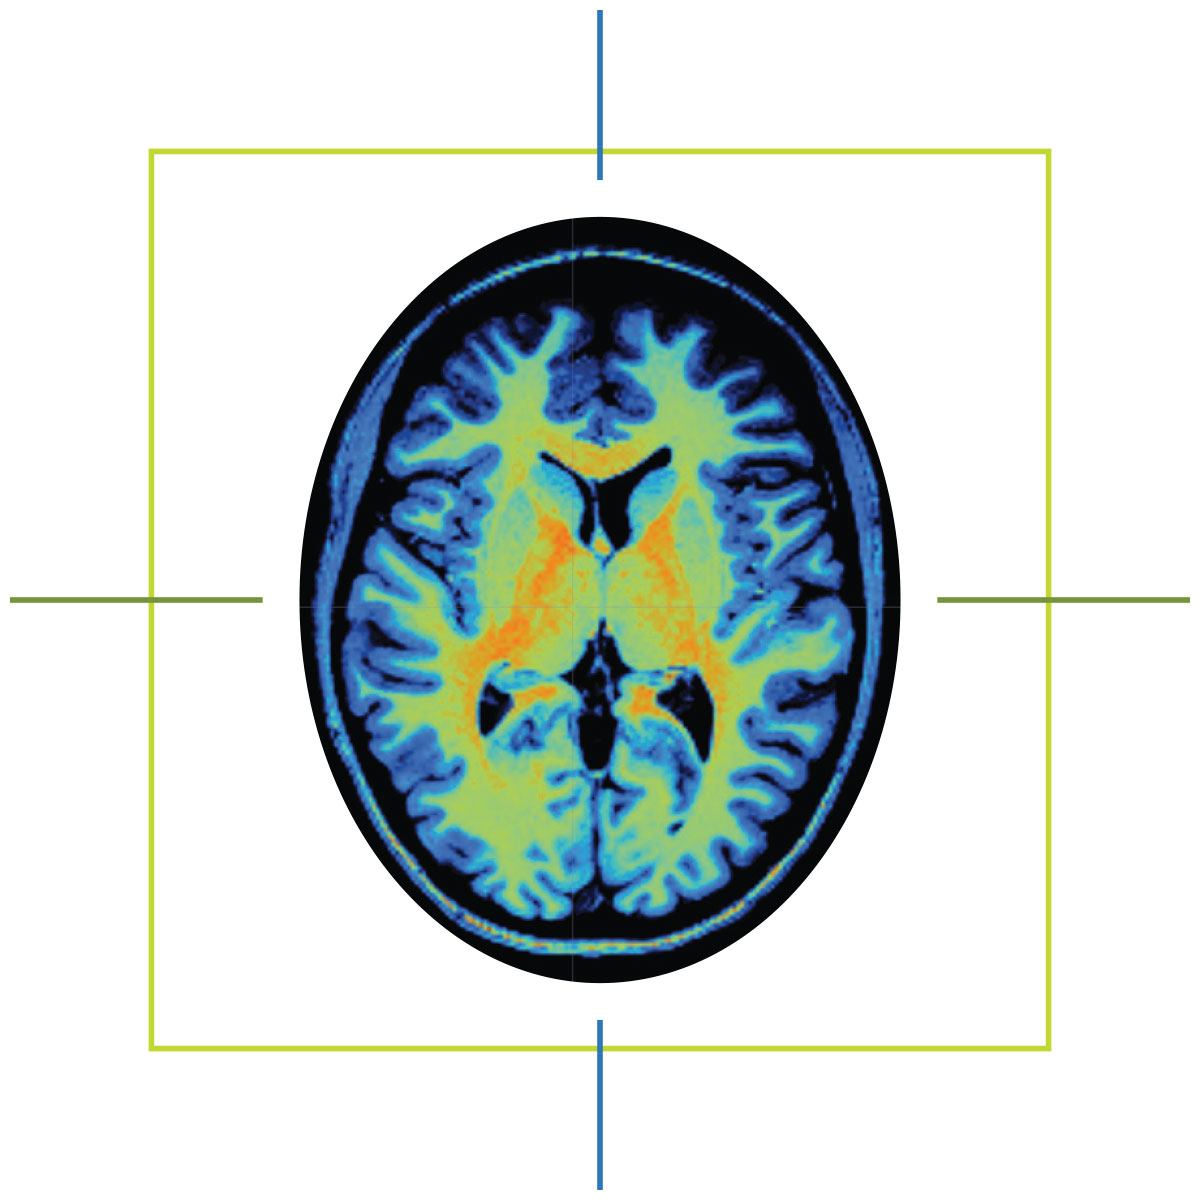

When Marcus Ryninger tells people how his life changed on May 1, 2015, he shows them an MRI scan saved to his phone.

Ten years ago, a massive stroke damaged the left side of his brain, leaving him with aphasia, a language disorder that affects communication. In the months that followed, Marcus and his wife, Marsha, found themselves at the University of South Carolina, where researchers from the Center for the Study of Aphasia Recovery performed an MRI.

He also knew his speech would never return to how it was before the stroke. But after seeing the scan of his brain — the dark hole of necrotic tissue on one side, the vibrant patchwork of healthy tissue on the other — the man who spent 30 years as a mechanic and quality control supervisor in the Navy understood: The stroke had not taken his determination.

“It helped me see what damage was done,” Marcus says. “I worked on airplanes. You have to find what’s broken and fix it. And the brain, that’s me. I know, ‘Oh, this part is broken. I have to fix this side.’ It made a difference for me.”

Before hospitals began using magnetic resonance imaging machines, or MRIs, for clinical use in the 1980s, physicians had a limited window inside the human body. X-rays could capture images of a patient’s bones. CT scans could even see soft tissues like muscles and organs. But both imaging methods exposed patients to ionizing radiation, and both were poorly suited to distinguish soft tissue variations critical for identifying ligament issues, brain anomalies and some types of tumors.

MRIs are commonplace in hospitals today, but most have a magnetic field strength of 1.5 Teslas or less. The McCausland Center’s scanner is a 3 Tesla, twice the strength of typical MRIs.

If you think of those rural clinics as wheel spokes, Fridriksson says, the hub is USC’s new Brain Health Center. Slated to open next to Prisma Health Richland in 2026, this state-of-the-art building will house two more MRI scanners: the state’s first ultra-high field 7 Tesla scanner and a wide-bore 3 Tesla scanner that can accommodate patients with larger builds.